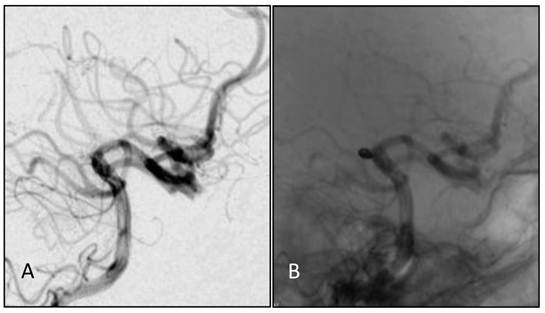

Figure 3

A,B: Angiograph of the vertebral artery showing developed posterior circulation with blood supply through the bilateral posterior communicating artery. No delay was observed in the anterior circulation angiograph, and from (B) a basilar apex aneurysm of about 3.2 mm could be observed.

Figure 4

A, B: DS angiographs taken after the aneurysm coil embolization. The aneurysm with dense embolization is not seen.

Figure 5

A,B: One year after embolizing the aneurysm with the endovascular approach, embolization was still in good condition, without recanalization.